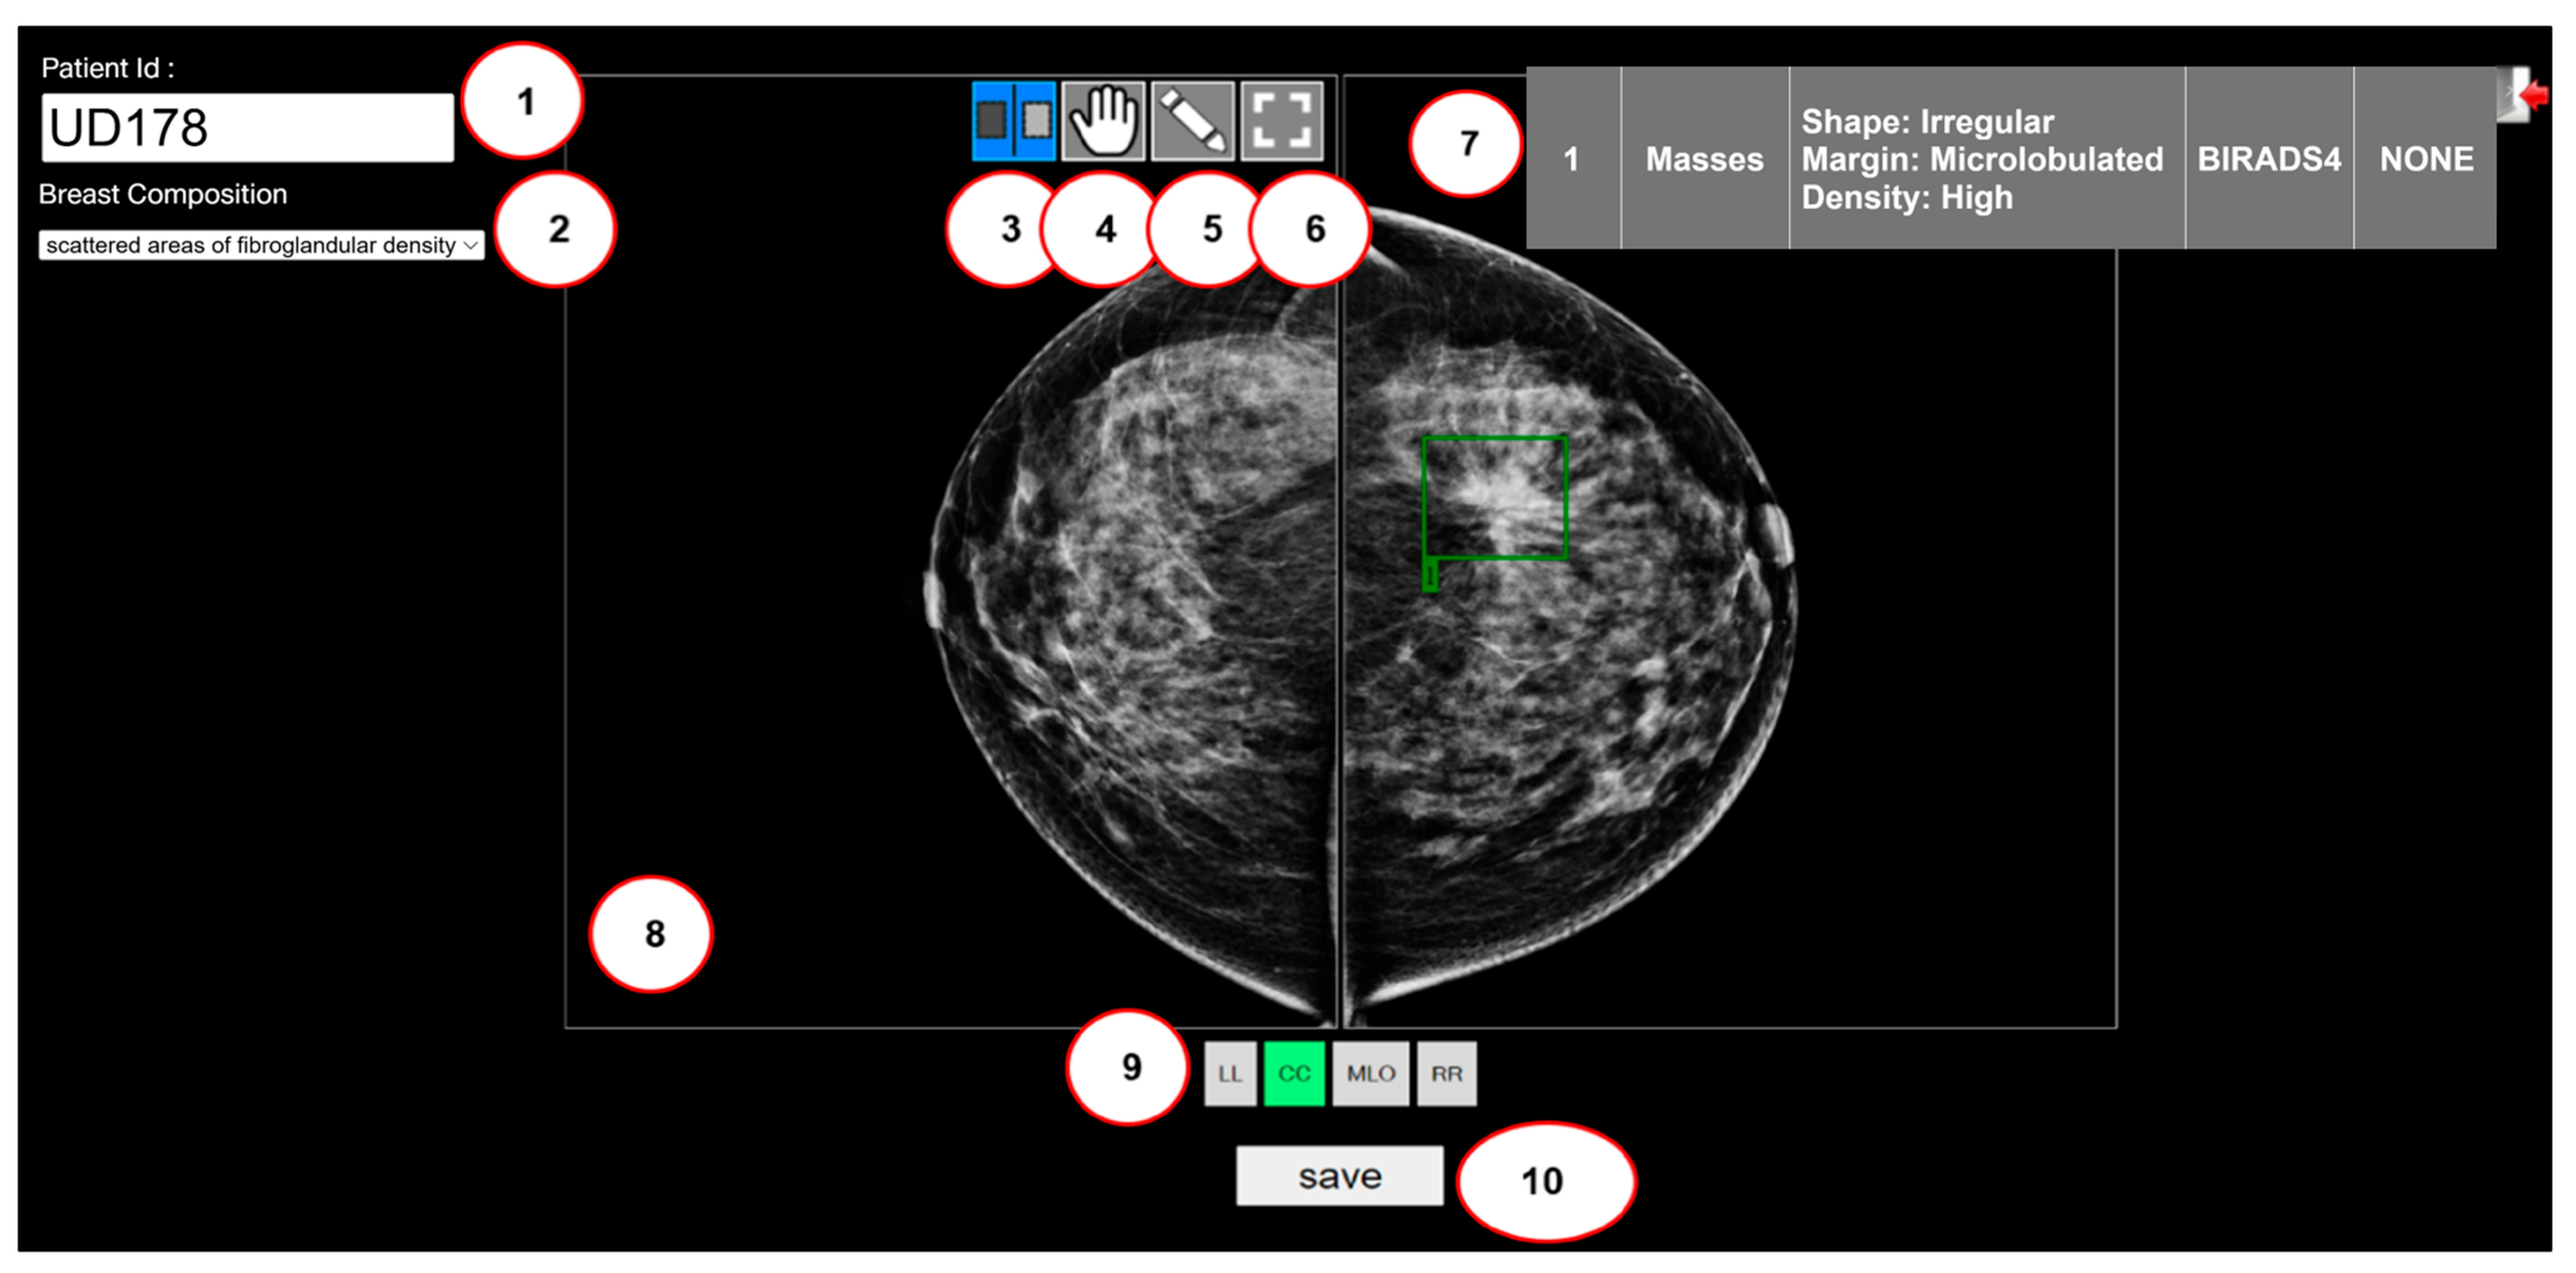

3.1. Graphical User Interface of the Custom Web-Based Labeling Tool

- Patient ID listing,

- Listing of breast compositions, which enumerate four breast densities: almost entirely fatty, scattered areas of fibroglandular density, heterogeneously dense, and extremely dense,

- Scrolling feature for individual breasts,

- Scrolling feature for dual breasts,

- Creating a bounding box,

- Resetting the image to its original view,

- Displaying the lesion type in detail,

- Displaying the mammograms,

- Quadruple view selection (CC: Craniocaudal, MLO: Mediolateral Oblique, LL: Left–Left, and RR: Right–Right) of the mammograms, and

- Saving annotated data.